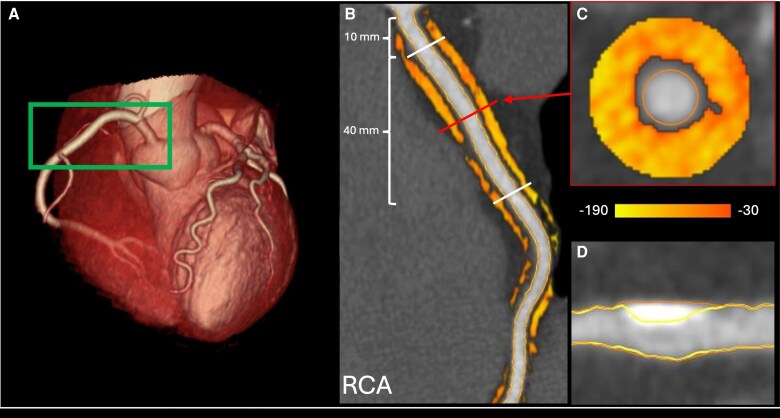

Aims: Pericoronary adipose tissue (PCAT) attenuation is a novel imaging biomarker of coronary inflammation associated with an increased risk of coronary artery disease (CAD). However, no studies have examined the relationship between chronic stress and PCAT. This study aimed to evaluate the intersection between chronic stress, inflammatory biomarkers, coronary plaque features, and PCAT attenuation.

Methods and results: A total of 98 participants without known CAD were included. PCAT attenuation, total plaque volume (TPV) quantification, and vulnerable plaque features were assessed by coronary CT angiography and chronic stress was measured by hair cortisol concentration (HCC) and vital exhaustion questionnaire. Regression models were used to analyse associations of PCAT with the inflammatory biomarkers interleukin-6 (IL-6) and tumour necrosis factor-α (TNF-α), TPV, vulnerable plaque features, and coronary stenosis. Moderating analyses were performed to test whether chronic stress modulated the association between inflammatory biomarkers and PCAT attenuation. PCAT attenuation was significantly associated with IL-6 (mean difference 1.05, 95% CI 0.21-1.89, P = 0.014), TNF-α (mean difference 0.60, 95% CI 0.06-1.13, P = 0.027), and a greater TPV (mean difference 3.51, 95% CI 0.02-7.00, P = 0.048), but not vulnerable plaque features or coronary stenosis. HCC (interaction term -0.12, 95% CI -0.22 to -0.02, P = 0.019) and vital exhaustion (interaction term 0.13, 95% CI 0.01-0.25, P = 0.024) moderated the relationship between IL-6, but not TNF-α, and PCAT attenuation.

Conclusion: This study suggests that circulating inflammatory biomarkers are associated with PCAT attenuation, which was further correlated with TPV. Chronic stress may moderate the relationship between inflammatory cytokines and PCAT attenuation.